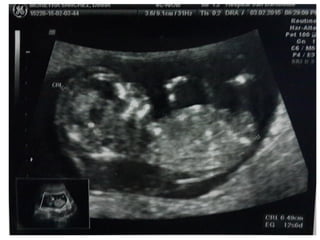

TRANSLUCENCIA NUCAL

• Personal entrenado, Ecógrafo de alta resolución

• Transabdominal, LCC:45-84mm

• Corte sagital medio. Feto en posición neutra.

• Incluyendo en la imagen sólo cabeza y tórax.

• Magnificación de la imagen(75%).

• Calipers emplazados de interno- interno de los bordes de la

TN y en sentido perpendicular.

• Diferenciar el amnios de la piel

TRANSLUCENCIA NUCAL • Personalentrenado, Ecógrafo de alta resolución • Transabdominal, LCC:45-84mm • Corte sagital medio. Feto en posición neutra. • Incluyendo en la imagen sólo cabeza y tórax. • Magnificación de la imagen(75%). • Calipers emplazados de interno- interno de los bordes de la TN y en sentido perpendicular. • Diferenciar el amnios de la piel